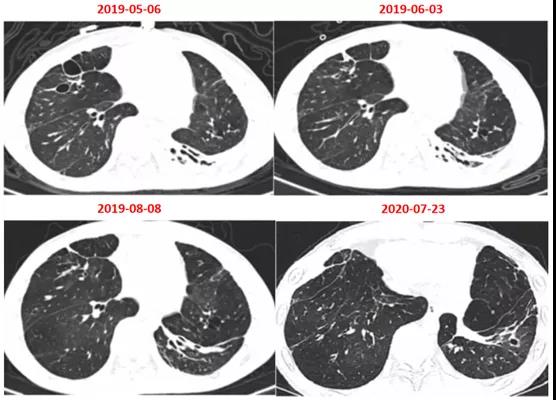

出院后患者复查胸部CT(图12)。

图12 出院后患者复查胸部CT

陈淮教授读片:5月6日患者胸部CT仅见局部囊腔,6月3日,囊腔基本消失,左下肺不张和实变。1年后,患者肺部复张,仅余少量条索改变。患者康复。